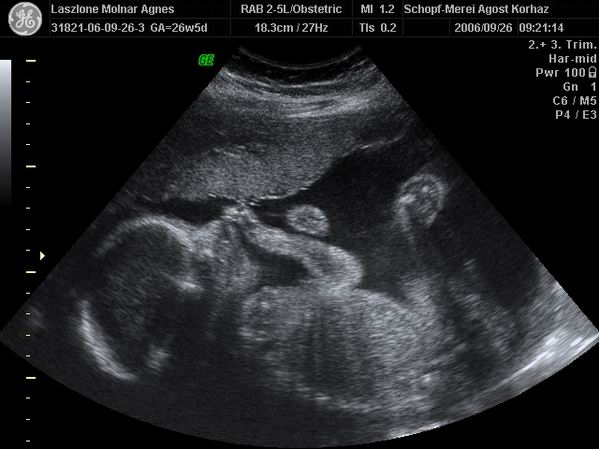

[img][img]https://www.babanet.hu/tarsalgo/attachments/1198169906.7709.jpg[/img] Anna 13-14 hetesen

[/img Kép 28 hetesen

[img][img]https://www.babanet.hu/tarsalgo/attachments/1198170005.3282.jpg[/img] 28 hetes 4D-s [/img]